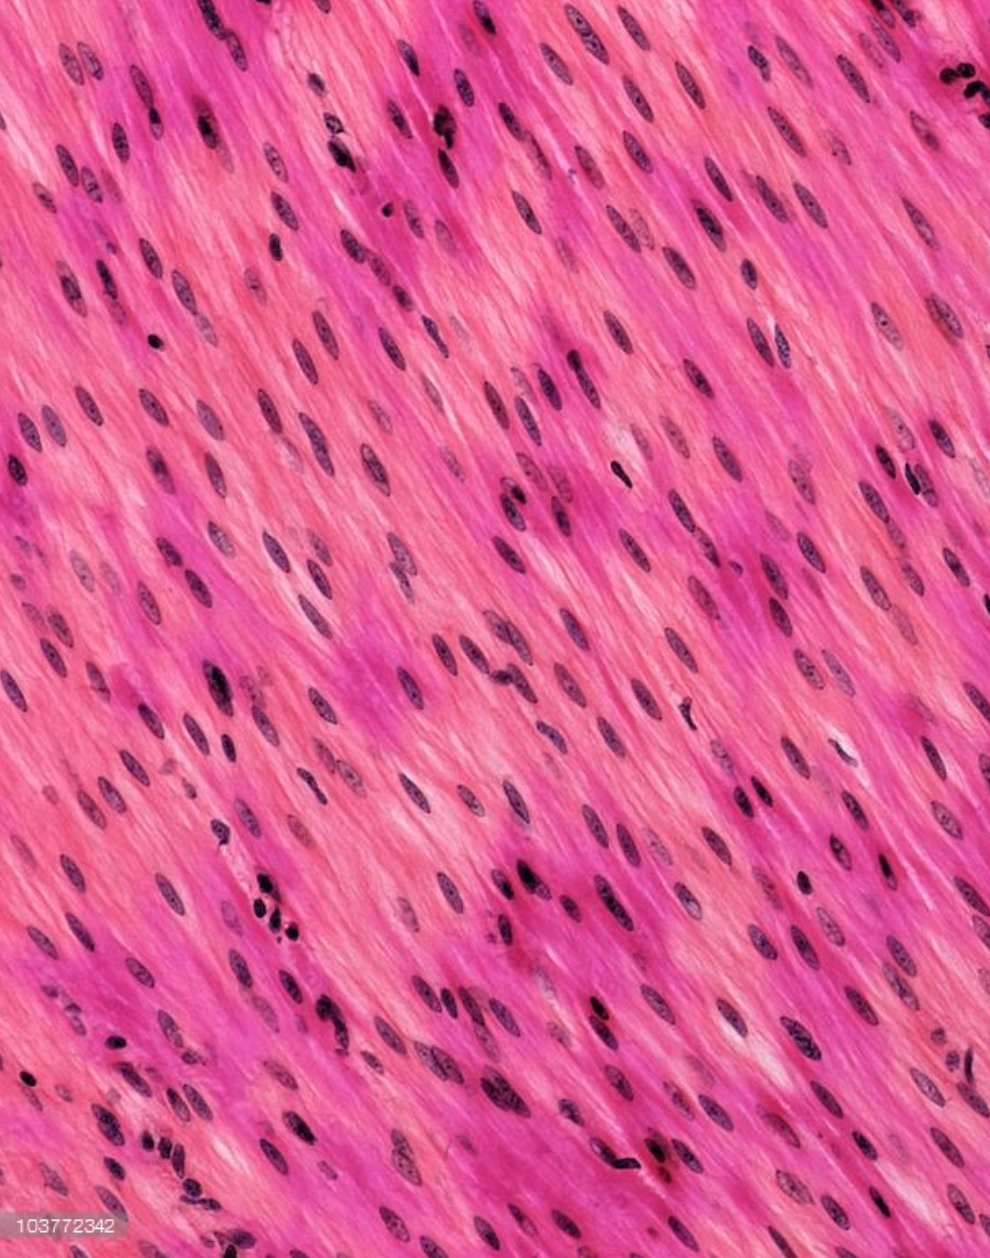

Smooth Muscle

Dense Regular Connective Tissue (description)

Parallel arrangment of collagen fibers